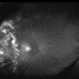

- OCTA, OCT Angiography, ultra-wide field imaging

TowardPi BMizar 400khz - Description

- Ultra-wide field OCT angiography of a 39 year-old healthy male. The photo attempts to explore retinal vasculature up to the ora serrata.